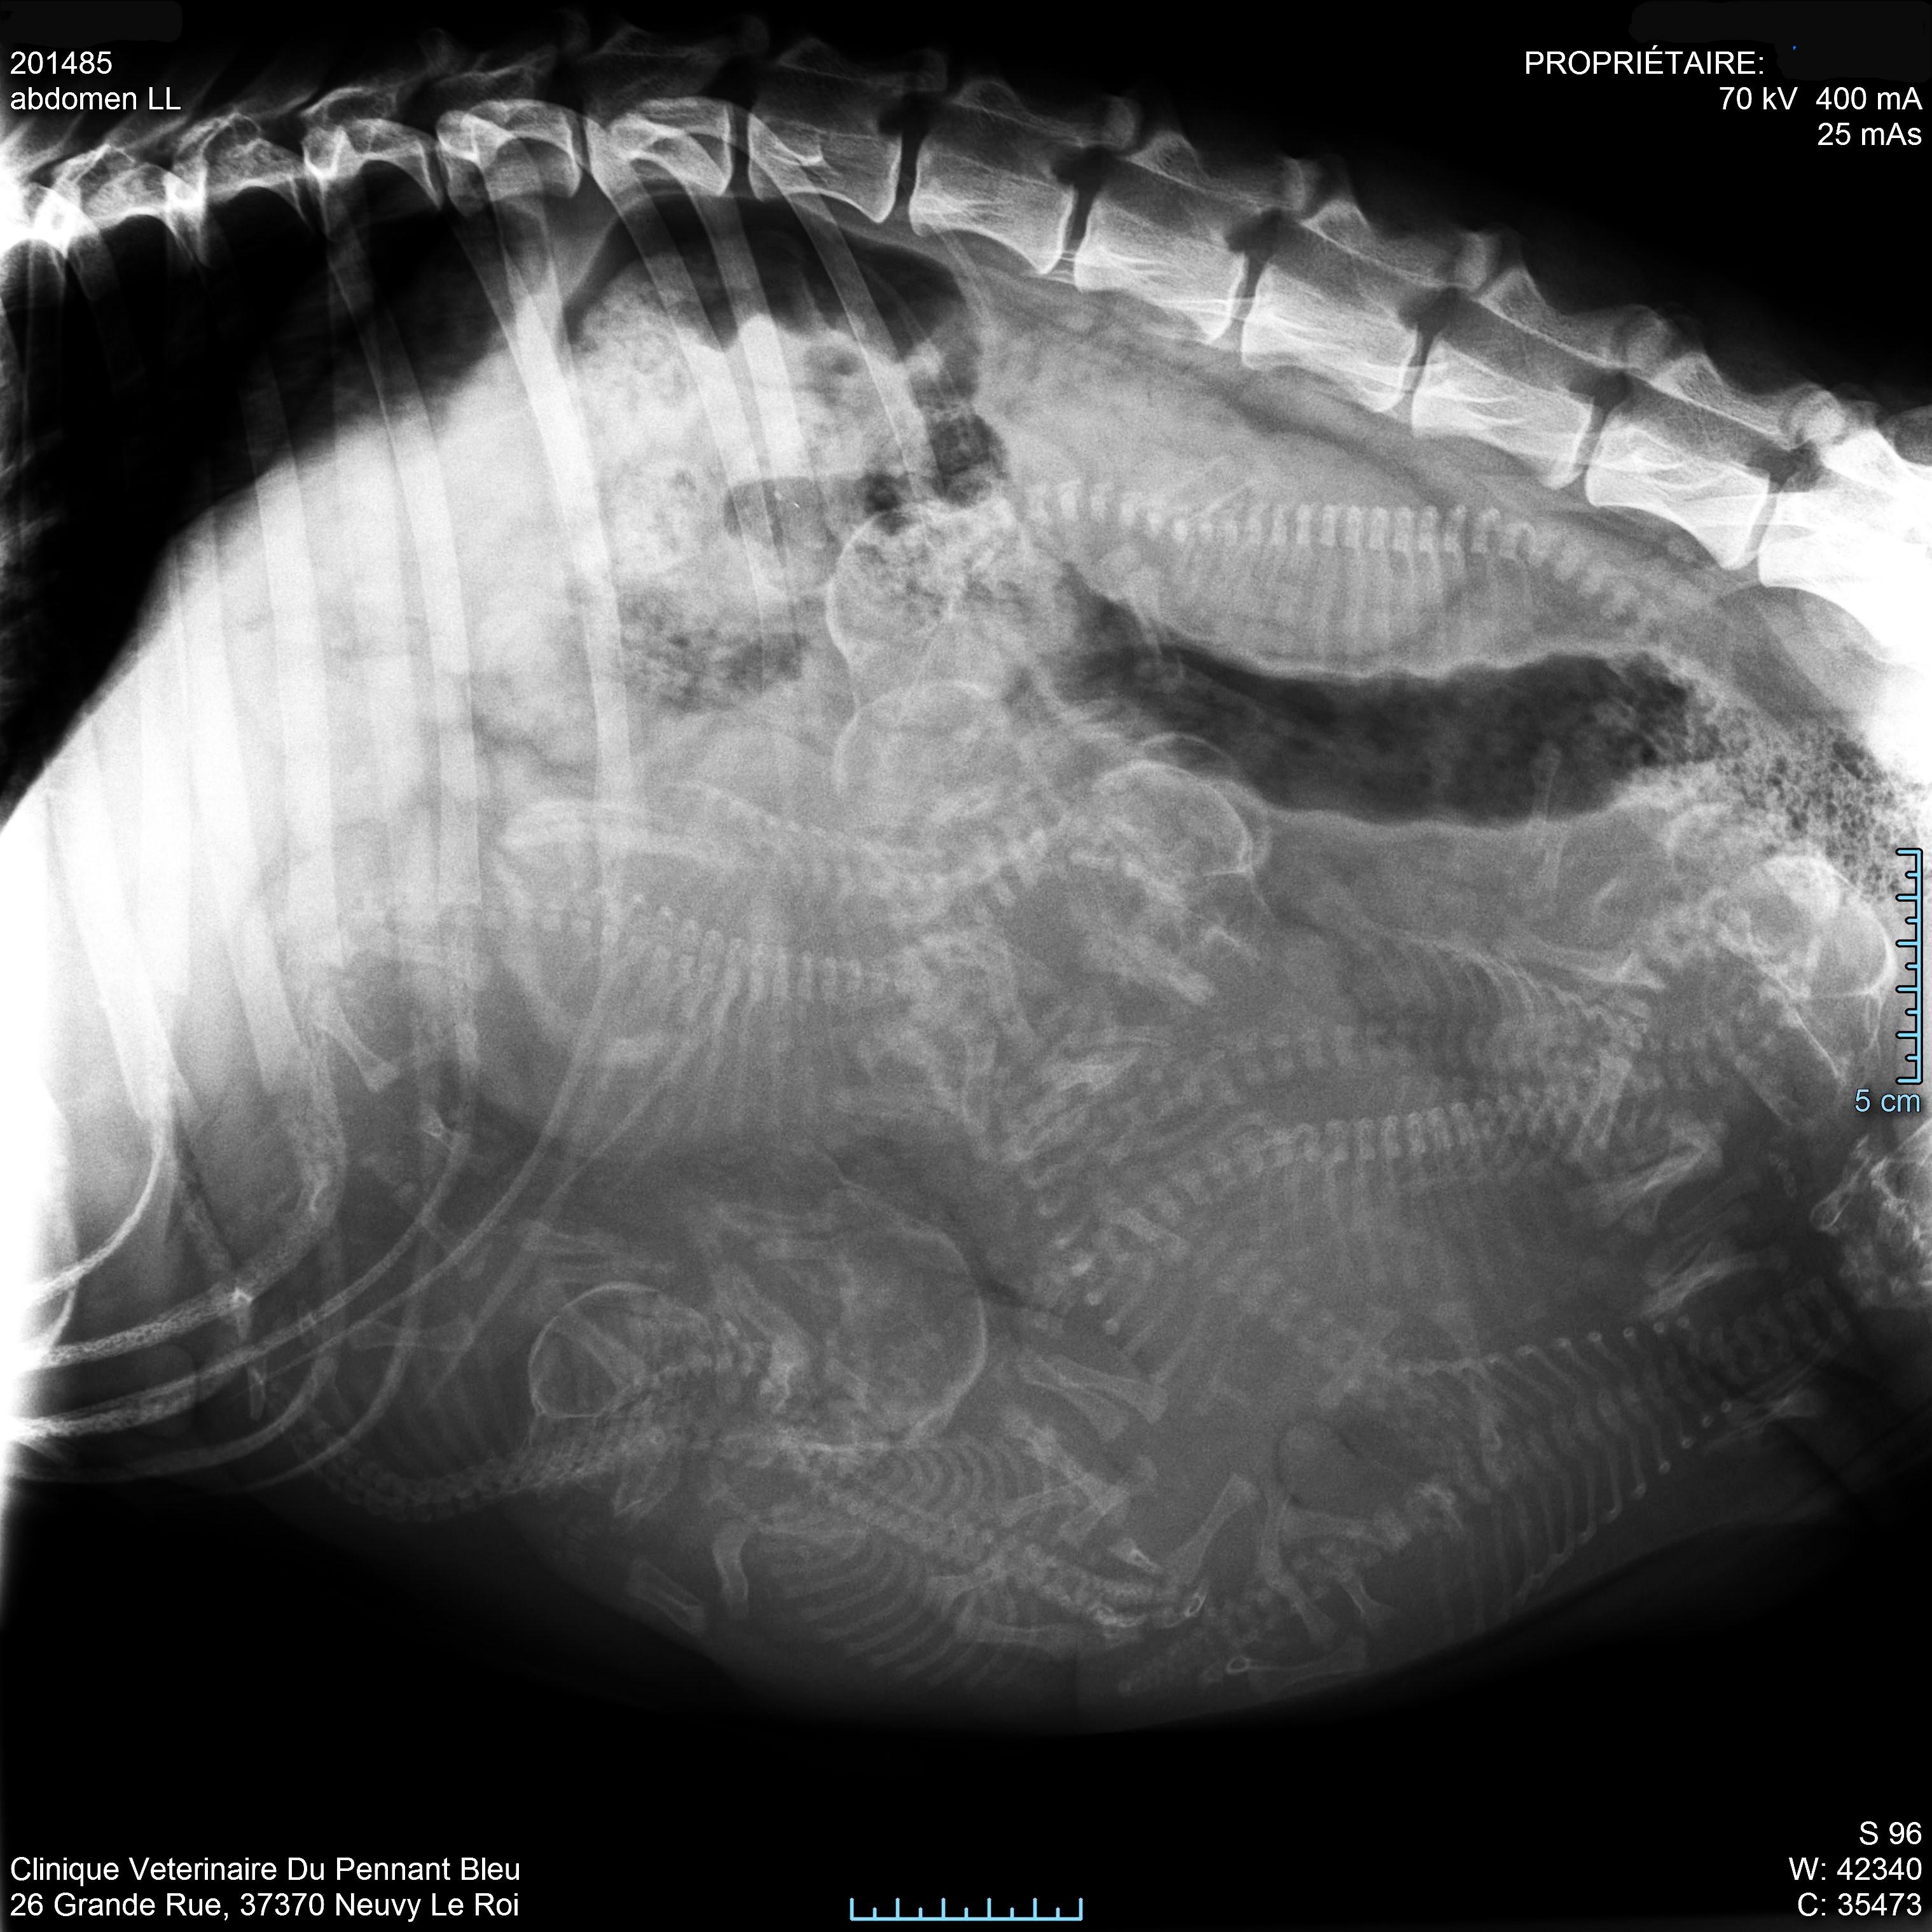

Radiographie abdominale

Elle permet de visualiser différents organes de l'abdomen. Elle est également utilisée pour la recherche par exemple de corps étrangers dans le tube digestif. Pour une meilleure visualisation de l'ensemble du tube digestif, il est parfois nécessaire d'utiliser des produits de contraste.

chienne gestante